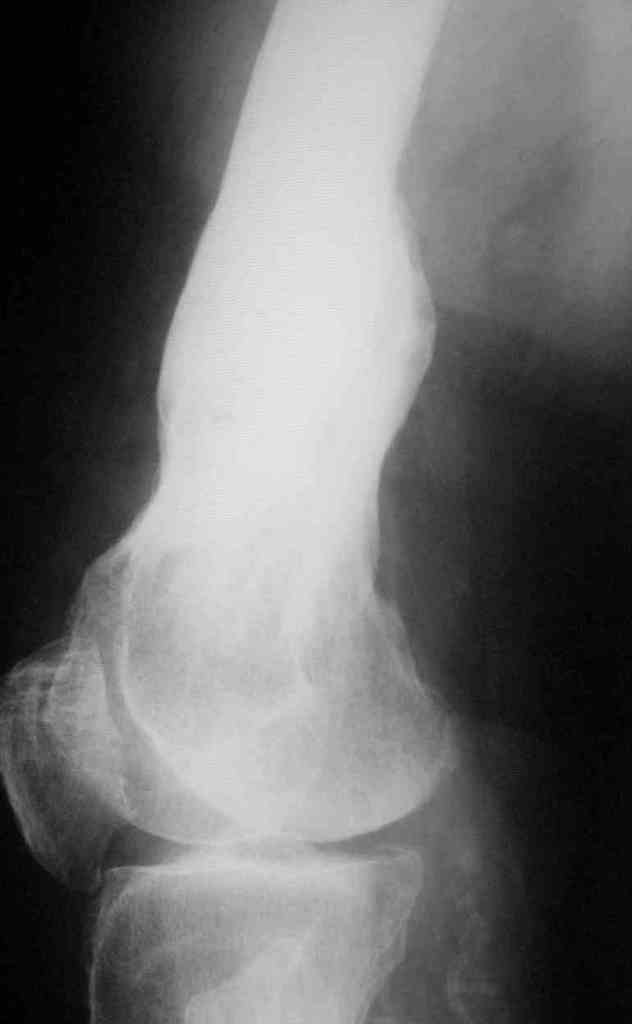

Пациент 69 лет. лечился по поводу перелома н/3 левого бедрамного лет

назад: несостоятельность внутреннего синтеза - АВф- хр. остеомиелит,

свищевая форма с периодическими рецидивами. Результат - укорочение

левого бедра 8 см.

В приложении рентгенограммы и внешний вид бедра.

Имя     : боковая Т.JPG